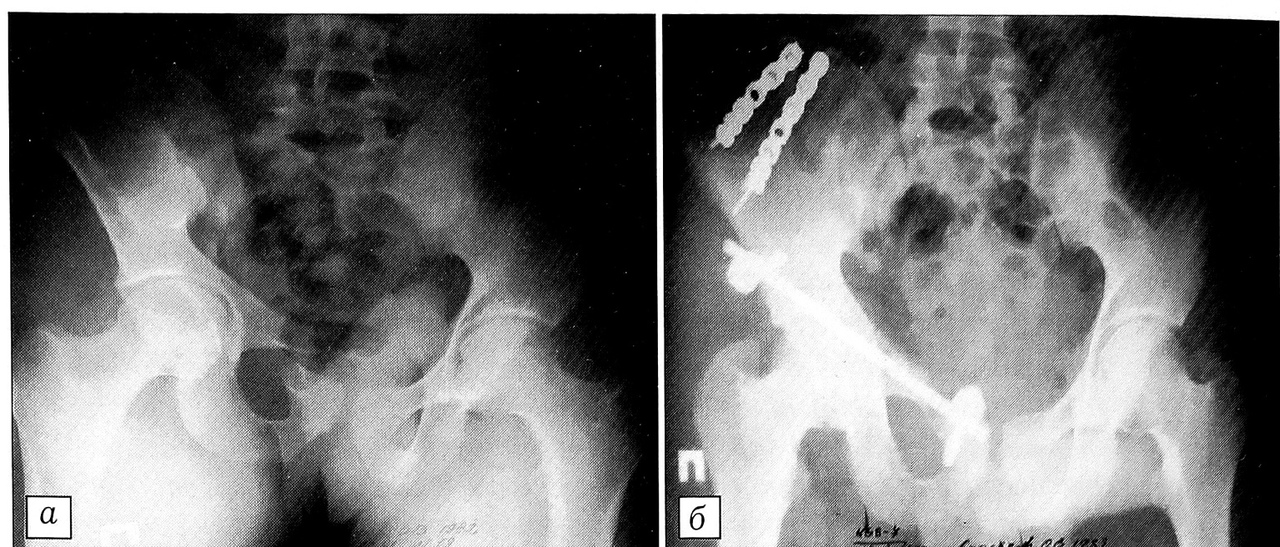

Если переломы ветвей лонных костей сопровождались разрывом лонного симфиза, для его фиксации применяли накостные опоры системы в виде одной или двух реконструктивных пластин с 3~5 отверстиями (рис. 2).

Рис. 2. Пострадавший 27 лет с абсолютно нестабильным повреждением таза: закрытым переломом ветвей левой лонной кости и левой боковой массы крестца. Произведена фиксация тазового кольца с использованием накостных опор. а — компьютерная томограмма таза при поступлении больного в клинику; б — рентгенограмма таза после оперативного лечения.

Кость обнажали только в месте введения винтов на протяжении 2-4 см. В случае необходимости дополнительно осуществляли доступ к остистым отросткам позвонков и их резекцию на уровне проведения стержня. Затем корнцангом формировали канал под длинными мышцами спины над крестцом, позвоночником или, если производили остеосинтез крыла подвздошной кости, под кожей над ее гребнем. Через подготовленный канал проводили отмоделированный по форме стержень; ориентируясь на него, вкручивали винты, затем собирали конструкцию, используя прижимные шайбы и поперечные штанги. С помощью внешнего репозиционного устройства сопоставляли отломки до приемлемого их положения и жестко фиксировали систему гайками (рис. 3).

Рис. 3. Пострадавший 17 лет с абсолютно нестабильным повреждением таза: закрытым переломом обеих ветвей правой лонной кости, полным вертикальным переломом крыла правой подвздошной кости со смещением отломков. Произведена внутренняя стабилизация таза с использованием двух реконструктивных пластин и минимально инвазивной стержневой системы. a — рентгенограмма таза при поступлении больного в клинику; б — после оперативного лечения.